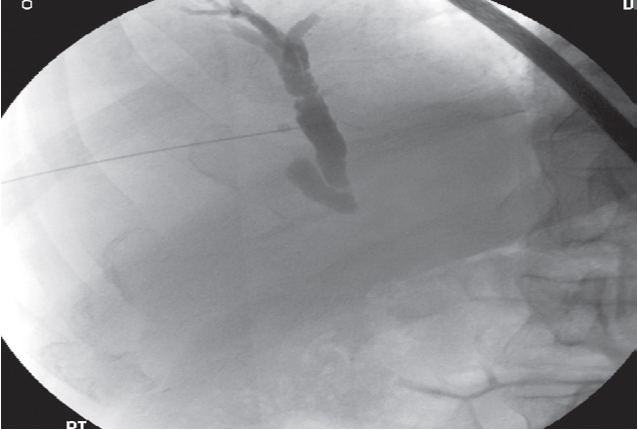

Percutaneous transhepatic cholangiogram (PTC):